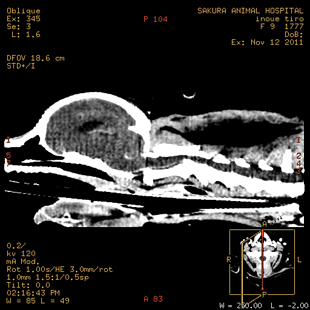

椎間板ヘルニア(頚部)